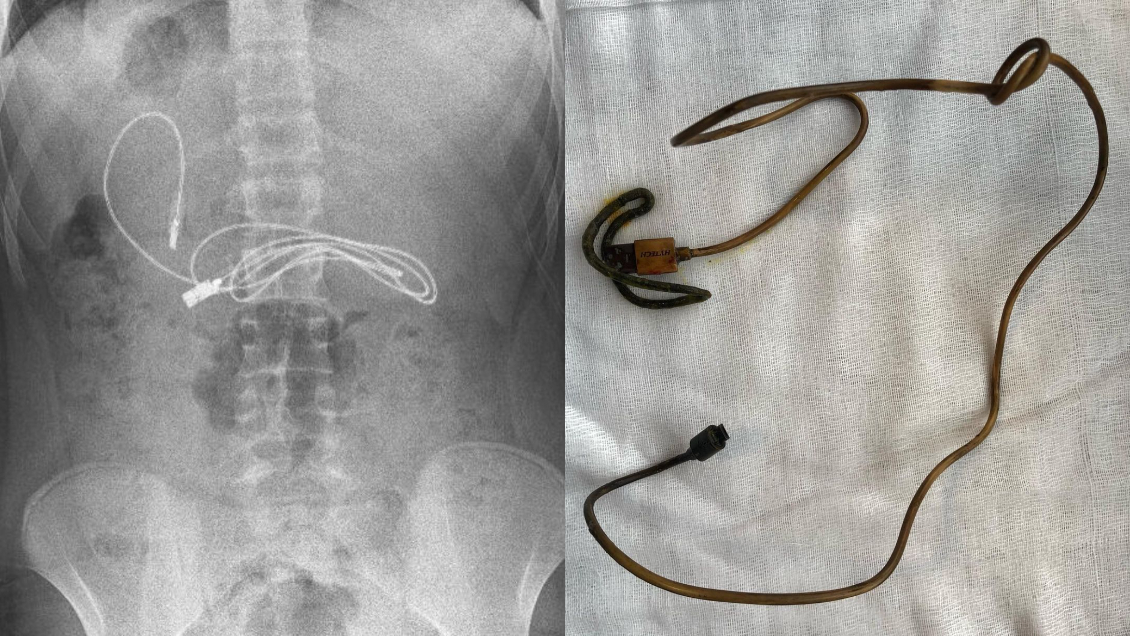

Un equipo médico de Turquía extrajo un cable USB de un metro de largo junto con un collet para cabello del estómago de un adolescente que fue hospitalizado tras presentar náuseas y vómitos.

Según informaron los medios locales, el jefe del departamento de gastroenterología, hepatología y nutrición pediátrica del Hospital de la Universidad de Fırat (FÜ), Yasar Dogan, solicitó una endoscopia para observar en detalle el estómago del joven de 15 años y así remover los objetos.

"Tuvimos dificultades para quitar el cable, ya que un extremo del cable había pasado al intestino delgado. Pero el procedimiento se completó sin ningún problema", señaló el profesional.